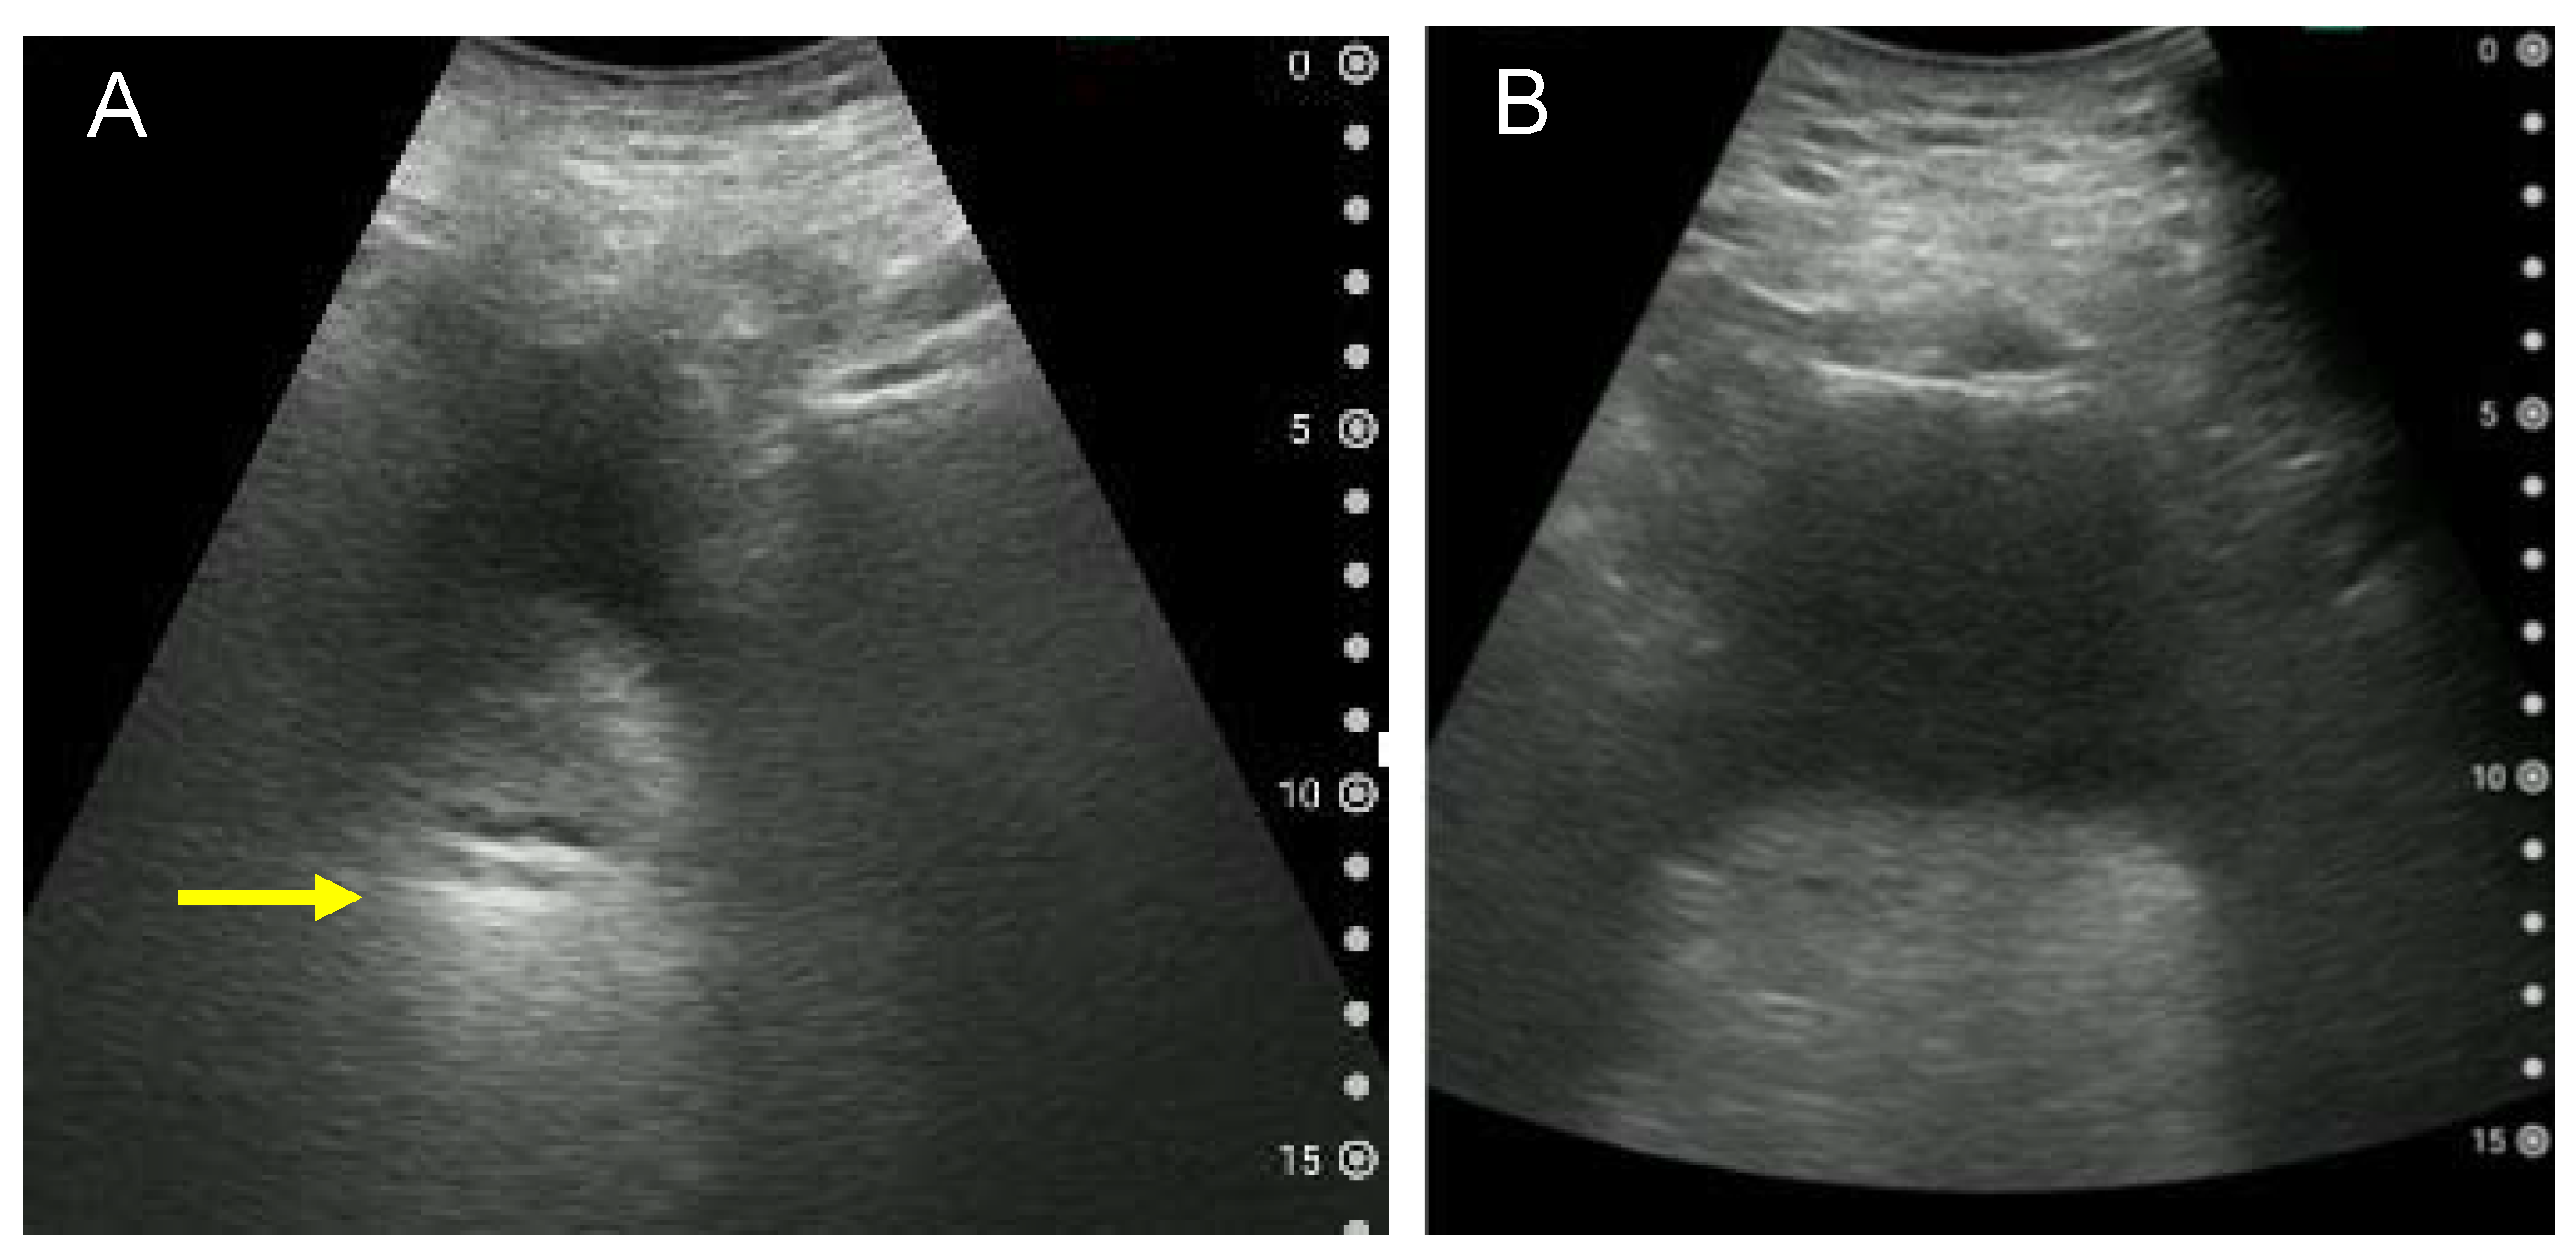

3.4. Findings That Need to Be Differentiated: Paradoxical Diarrhoea